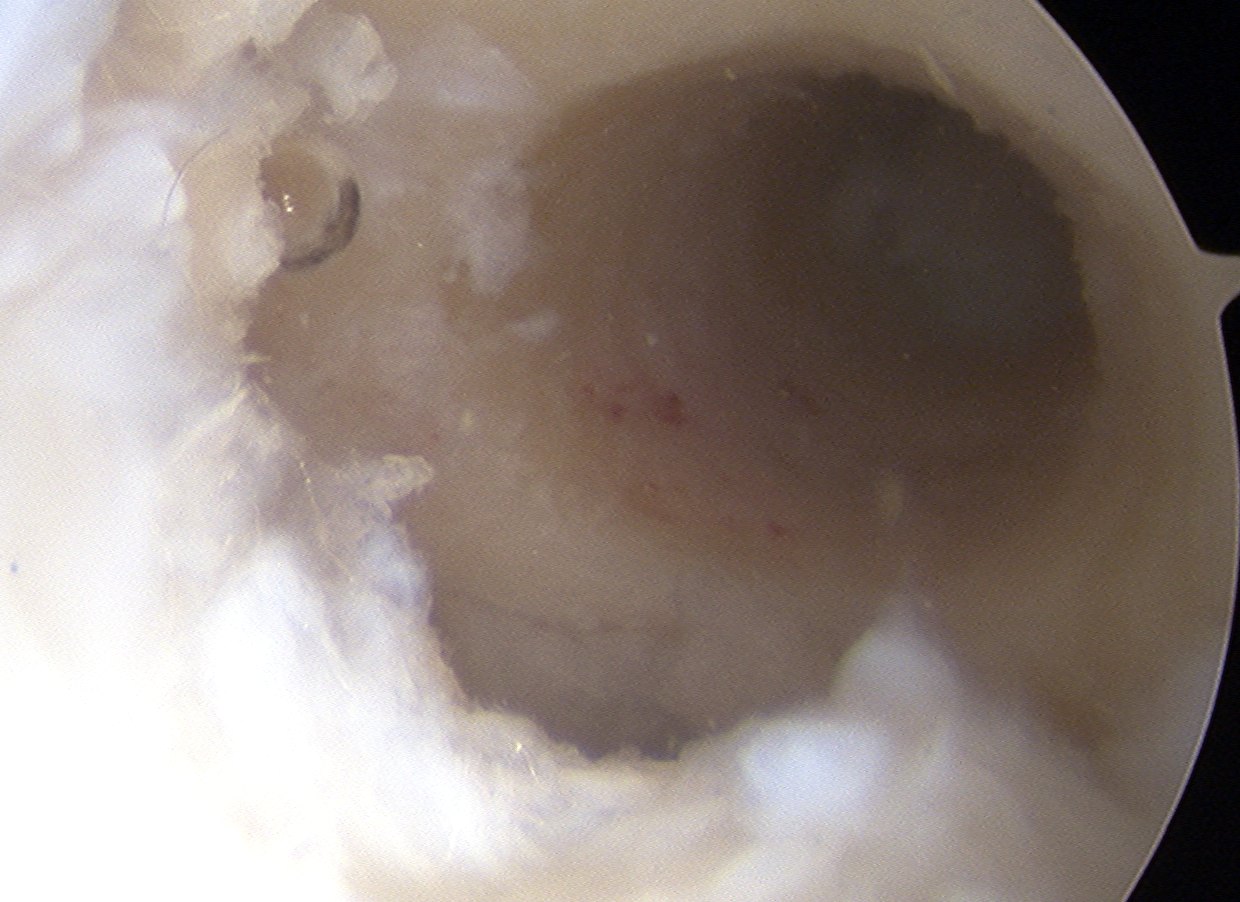

Failed ACL with tibial tunnel too posterior and with lysis

Tunnels debrided / redrilled and synthetic bone plugs inserted